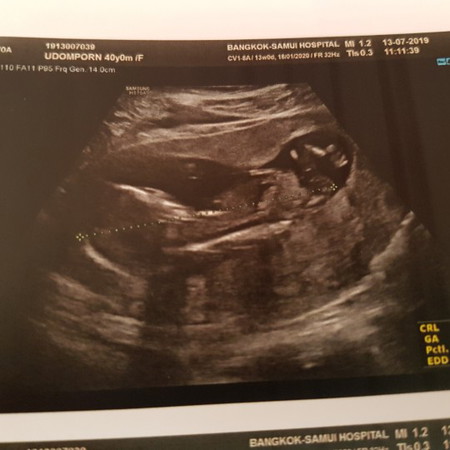

น้อง13 วีคแต่ตัวยาว 9 เซน

คุณหมอบอกว่าอาจจะ 14 วีคนั้นจากความยาวของตัว แต่เราก็มั่นใจนะว่าเม้นเรามาครั้งสุดท้ายเรามา 13 เมษาเพราะสงกรานต์เราไม่ได้เล่นน้ำ

ของเราตอนซาวด์ประเมินออกมาโตกว่าอายุจริงตลอดนะคะ 1Wบ้าง Wกว่าๆบ้าง ไม่แปลกค่า น้องอาจจะตัวโต